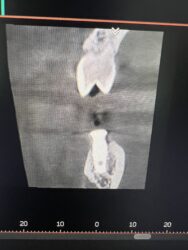

What are your thoughts on what this radiolucent area in the anterior mandible could be? Should I be concerened with placing an implant into it?

I’m not sure just from those slices but more reward and less risk in other locations. Around the mandibular midline you have your superior and/or inferior foramina relative to the genial tubercle/mental spine which can very in size greatly from pt. to pt. and often times very apical where no teeth have been before you can have more variability…

100% in agreement with @restoredsmiles While the anterior mandible is easy pickings for implants, it is very important to pay attention to things like this in the x rays.

It looks like if you drill into that spot you may get a bleeder that might be difficult to manage. I would also recommend opting for modifying your plan to stay away from that finding.